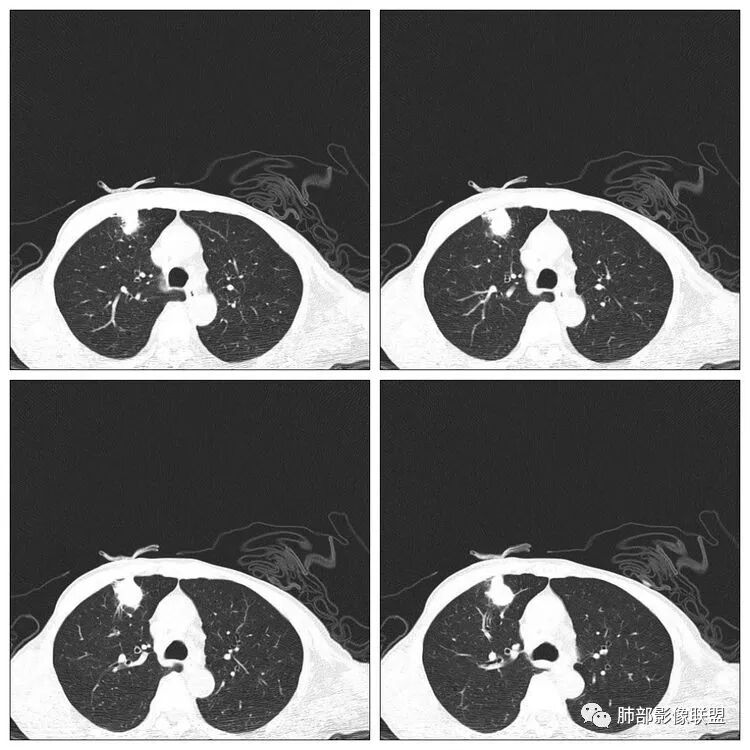

患者男性,70岁;既往有高血压病病史,还有冠心病病史;不嗜烟酒;因头昏入院,查胃镜病理提示鳞状细胞癌,胸部CT提示右上肺占位性病变。

南边:患者男性,70岁;既往有高血压病病史,还有冠心病病史;不嗜烟酒;因头昏入院,查胃镜病理提示鳞状细胞癌,胸部CT提示右上肺占位性病变。

老年男性,有胃癌可惜没增强南边:常规:1、转移瘤2、肺癌3、炎性病变为啥考虑炎性?小赵:局部边缘平直南边:

南边:宽基底与胸膜相连桃尖征、U型凹陷、刀切征密度均匀,按理这一部分就是典型的炎性病变的特点

南边:周围晕、细微毛刺都属于炎性特点这一部分单独拿出来类圆形,边缘光滑,按理恶性特征不明显;但是加在一起,转移瘤就不排除总体倾向于炎性,转移瘤不除外

1.胸膜下不规则结节影,密度不甚均匀,有浅分叶、长毛刺,周边有磨玻璃晕。

2.有胸膜牵拉,尽管收缩能力不强。支气管相关(有细小支气管止于病灶内侧),加之病灶孤立、边界不清带晕,这些都不是血道转移病灶的特点。

左锁骨上及纵隔未见肿大淋巴结,注意这是胃癌的淋巴转移路径。

3.病灶没有新旧不等、没有高密度,没有卫星灶,结核的支持点也不多。

综上,更支持慢性炎性病灶。隐球菌感染不能排除,无论是影像特点,还是患者不相关的临床表现。